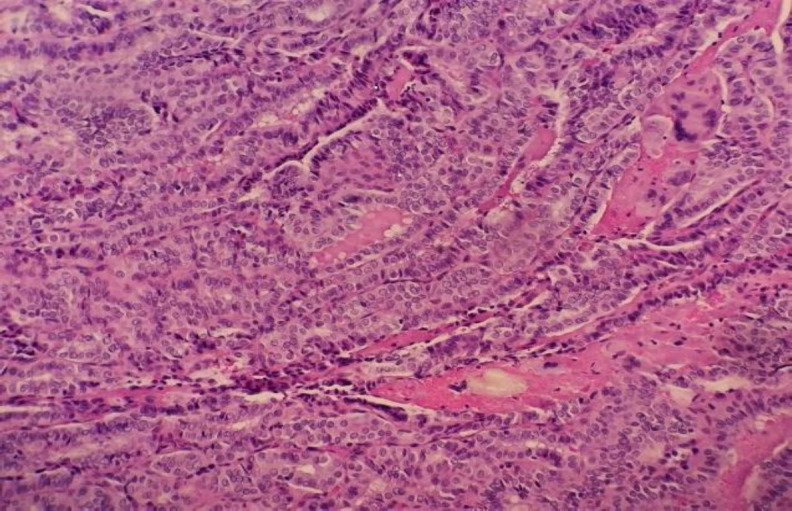

Case reports: We describe a novel case where primary papillary thyroid carcinoma (PTC) was found after a trans-oral excision of a tumor containing ectopic thyroid tissue at the posterior pharynx, an area not known to be a location for ectopic thyroid. Delays due to the COVID-19 pandemic resulted in regional cervical metastases and multifocal PTC. The female patient successfully underwent total thyroidectomy, selective cervical and central lymph node dissection, followed by adjuvant radioactive iodine ablation, with no evidence of distant metastases.